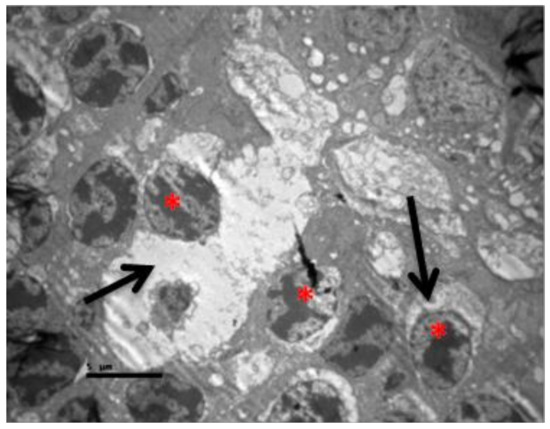

2.2. Group V

2.3. Group M